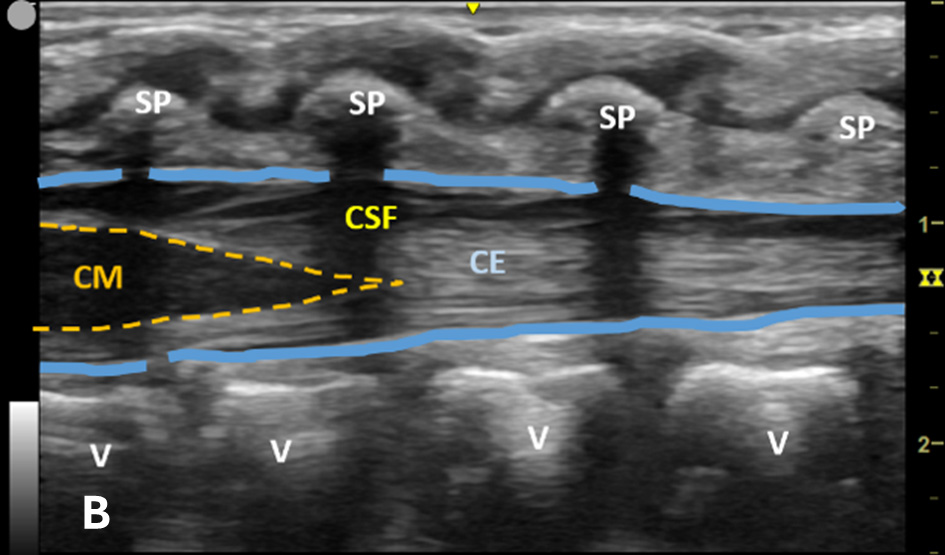

US-assisted LP is performed using the high-frequency linear transducer at the infant’s lower lumbar spine, with the patient either in a lateral recumbent position or an upright sitting position. The standard LP position, in which the neck and hips are flexed, should be used to locate the optimal site for needle insertion. Warm gel should be used during US to provide comfort and reduce the risk of hypothermia in infants. Align the transducer along the spinous process of the lumbar spine above the level of intercristal line to obtain a sagittal view of the spinal canal. The tapered CM is identified, below which any space is safe for needle insertion. The amount of anechoic cerebrospinal fluid (CSF) can be grossly compared in each space to locate the ideal LP site to obtain maximal CSF volume. (Figure 1A-B) The next step is to mark the skin at this optimal intervertebral level using a marking pen. Additionally, we recommend measuring the depth from the skin to the posterior border of the subarachnoid space using calipers, ensuring an angle of entry of 30–45 degrees. (Figure 1C) This allows the proceduralist to more precisely estimate the minimum needle depth needed to reach the subarachnoid space.

Figure 1A - Corresponding US image showing the target area of the lower spinal canal in sagittal/longitudinal view.

Figure 1B - Structures in the target area: SP (spinous process), CSF (cerebrospinal fluid), CM (conus medullaris), and CE (cauda equina).

Figure 1C - The minimum depth from the skin to the posterior border of subarachnoid space for needle entry using calipers, which is measured at 0.97 cm (yellow dotted line).